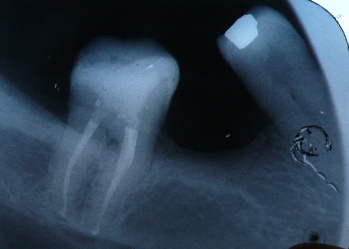

an X-ray of a molar tooth - after root canal treatmentroot filling

Here is a radiograph (X-ray) of a molar root filling with very curved roots on the left side of the picture. These root canals bend sharply near the end of the root. These two root canals were very difficult to work on! And even with all my gadgets I couldn't get all the way to ends of the roots there, so you can see that the root fillings on the left side are a millimeter or so short.